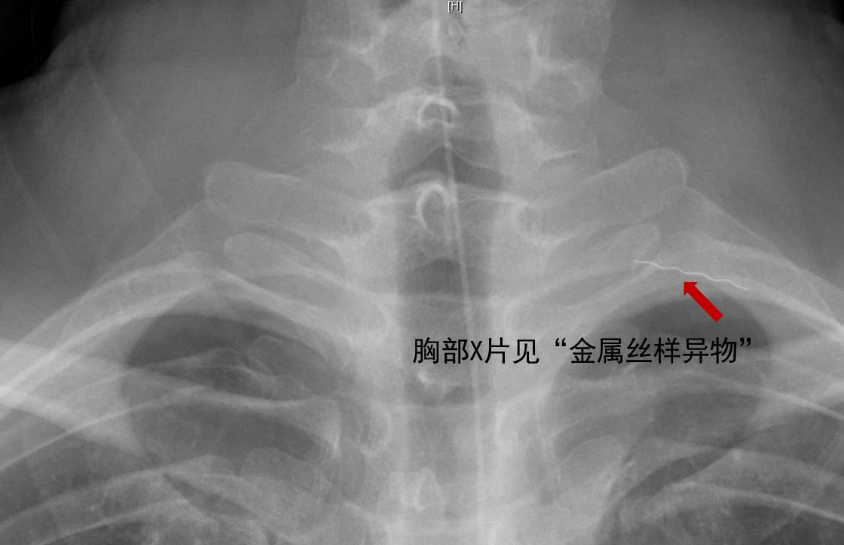

一听说颈部可能有异物,这可吓坏了石先生及家人。他立刻来到北京清华长庚医院耳鼻咽喉头颈外科做检查,接诊医生结合石先生的病史、查体及辅助检查,考虑他可能为经口进食了“金属丝”样的异物,然后异物刺入了食管,并在进食的过程中,导致异物穿透食管壁,进入食管周围间隙,最终“游走”进入颈部软组织中。

这种情况如不及时诊治,局部组织高度水肿,引起颈部感染,异物本身或感染倾犯颈部血管,导致动脉破溃出血,严重者可危及生命。于是,医生很快为石先生安排了颈侧切开异物取出术。手术中,果真从石先生左颈部的肌肉组织中取出了一根长约2厘米的螺旋状金属丝。